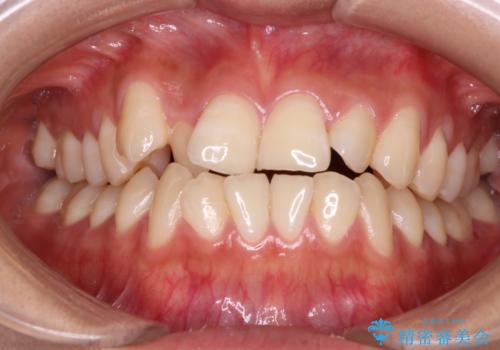

- 前歯のガタガタを主訴に来院されました。

インビザラインも提案しましたが、装着時間を確実に確保できるか不安ということもありワイヤー矯正を希望されました。